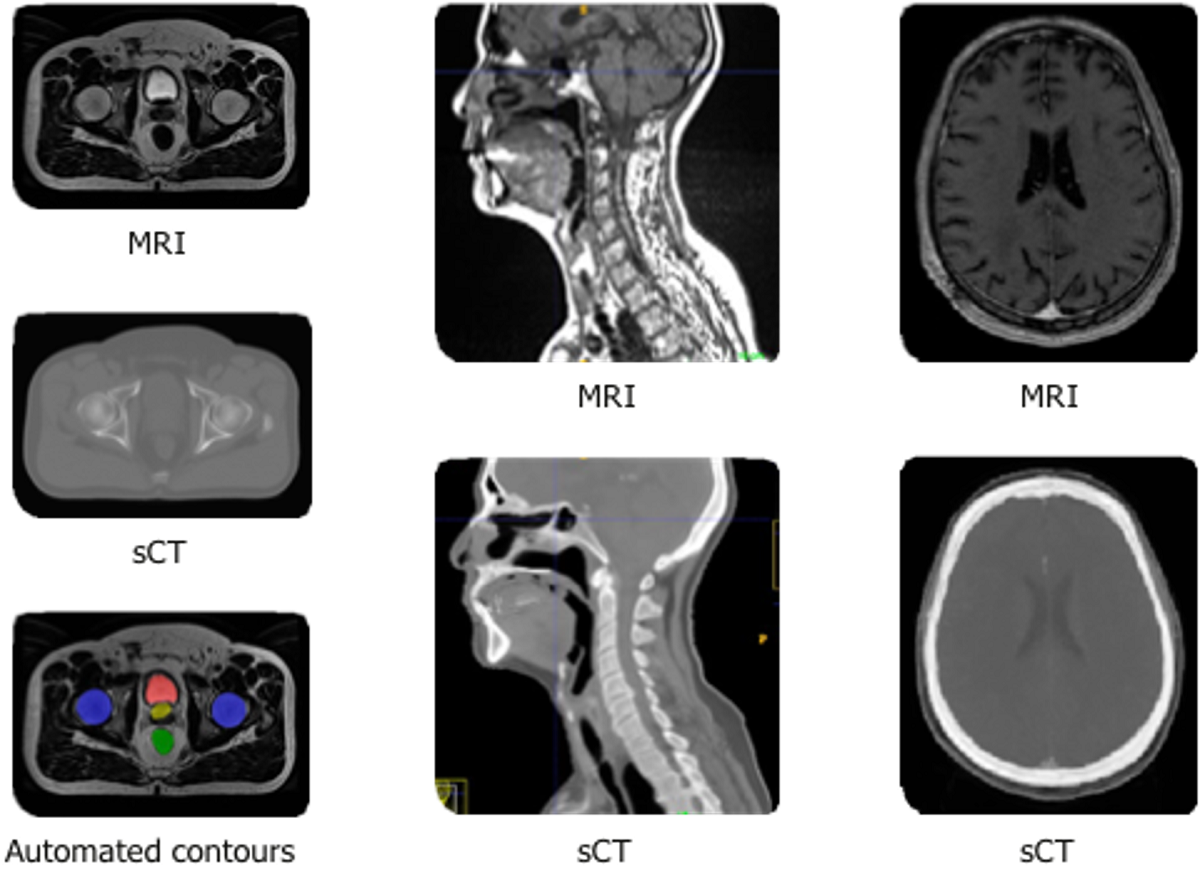

Enabling Radiation Oncology Treatment Planning with Advanced Imaging Different Medical Imaging Techniques Or what they can do? Medical scans help doctors diagnose. at uva radiology and medical imaging, we use each modality to perform multiple types of imaging tests to. Do you know what these tests involve? They create images using various forms of. the bmc methods collection “advances in medical imaging techniques” will showcase the latest advancements in. . Different Medical Imaging Techniques.